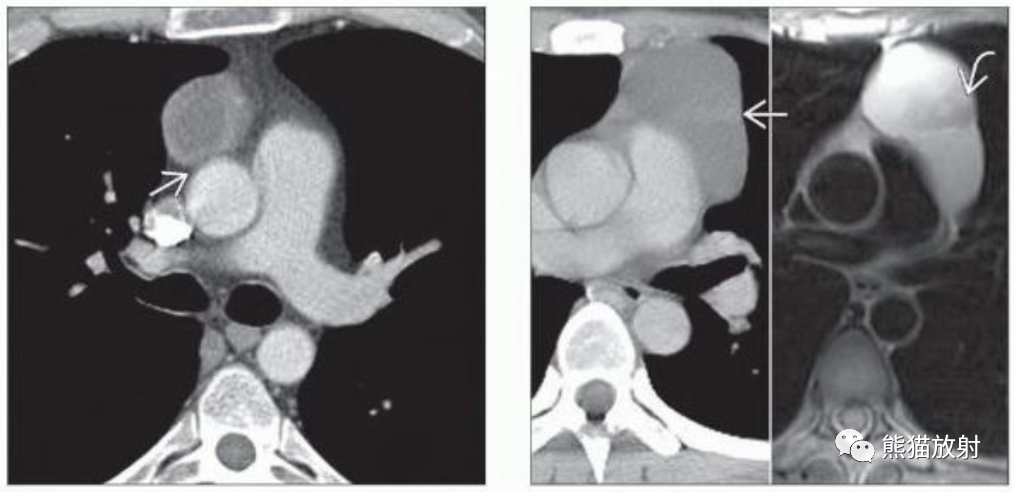

(左) 胸腺瘤,增强CT显示右前纵隔球形肿块,由于坏死中心呈低密度。与邻近升主动脉分界清晰(箭)。

(右) CECT和轴位T2WI显示左前纵隔囊性胸腺瘤并结节样软组织分隔,在MR上更为明显。纵隔囊肿出现壁结节应提示囊性肿瘤。